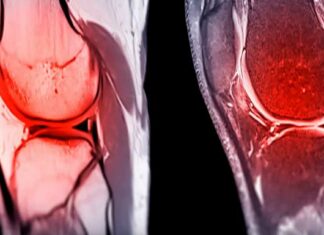

Cutting-edge biomaterial could help repair damaged joint cartilage

Cartilage is a strong, flexible connective tissue that protects the joints and bones and acts as a shock absorber throughout the body.

The cartilage...